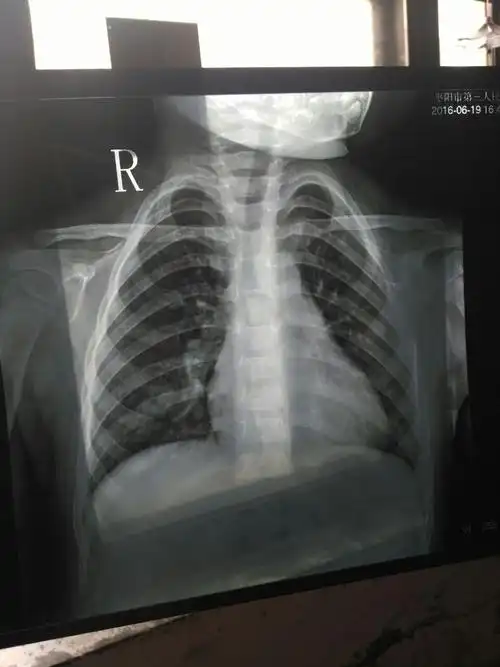

女童未及时就医诊断小儿支气管肺炎联合用药得以缓解

宝宝一岁支气管肺炎

孩子3周岁多点,支气管肺炎入院治疗,6天后,孩子明显好转,医生依然让

儿童胸片 大家帮忙分析一下!